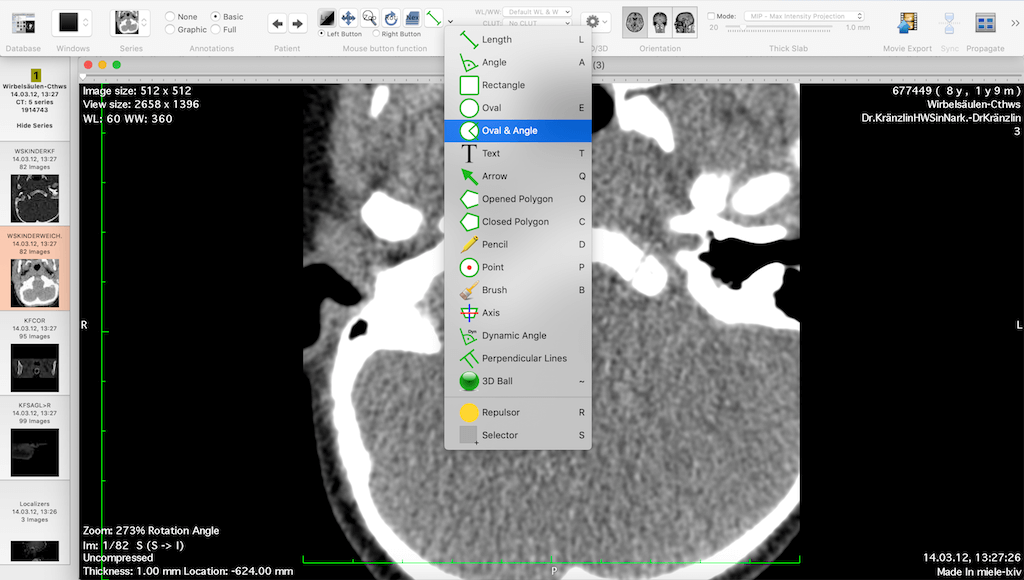

Horos is an open source DICOM viewer for Mac. It is actually the free version of an expensive DICOM viewer called Osirix MD, which is often considered to be the best DICOM viewer for Mac. It only runs on Mac OS, version 10.8 or higher. This software allows for most diagnostic techniques, including multiplanar reconstruction, maximum intensity projections, and volume rendering. It also has tools for manipulating images and making measurements.

One of the unique features of Horos is that it has a plug-in that allows uploading of images to Radiopedia, an online resource with a large number of reference cases and articles. Technical support is available through both phone and email. Horos, however, does not integrate to PACS free of cost. Cloud-based storage is available at an additional cost.

A free version of Osirix MD, called Osirix Lite, is also available to users. However, it does not allowing editing of imaging metadata, and image modifications come with a watermark. While this is good to get a feel for the parent software, it is not intended for regular medical use.

Miele LXIV is a free DICOM viewer for Mac operating systems. It has advanced features including MPR, MIP, volume rendering, and image fusion. In addition, it also allows 4D viewing of cardiac CTs. It is PACS-integrated and can send and receive files from a PACS database.